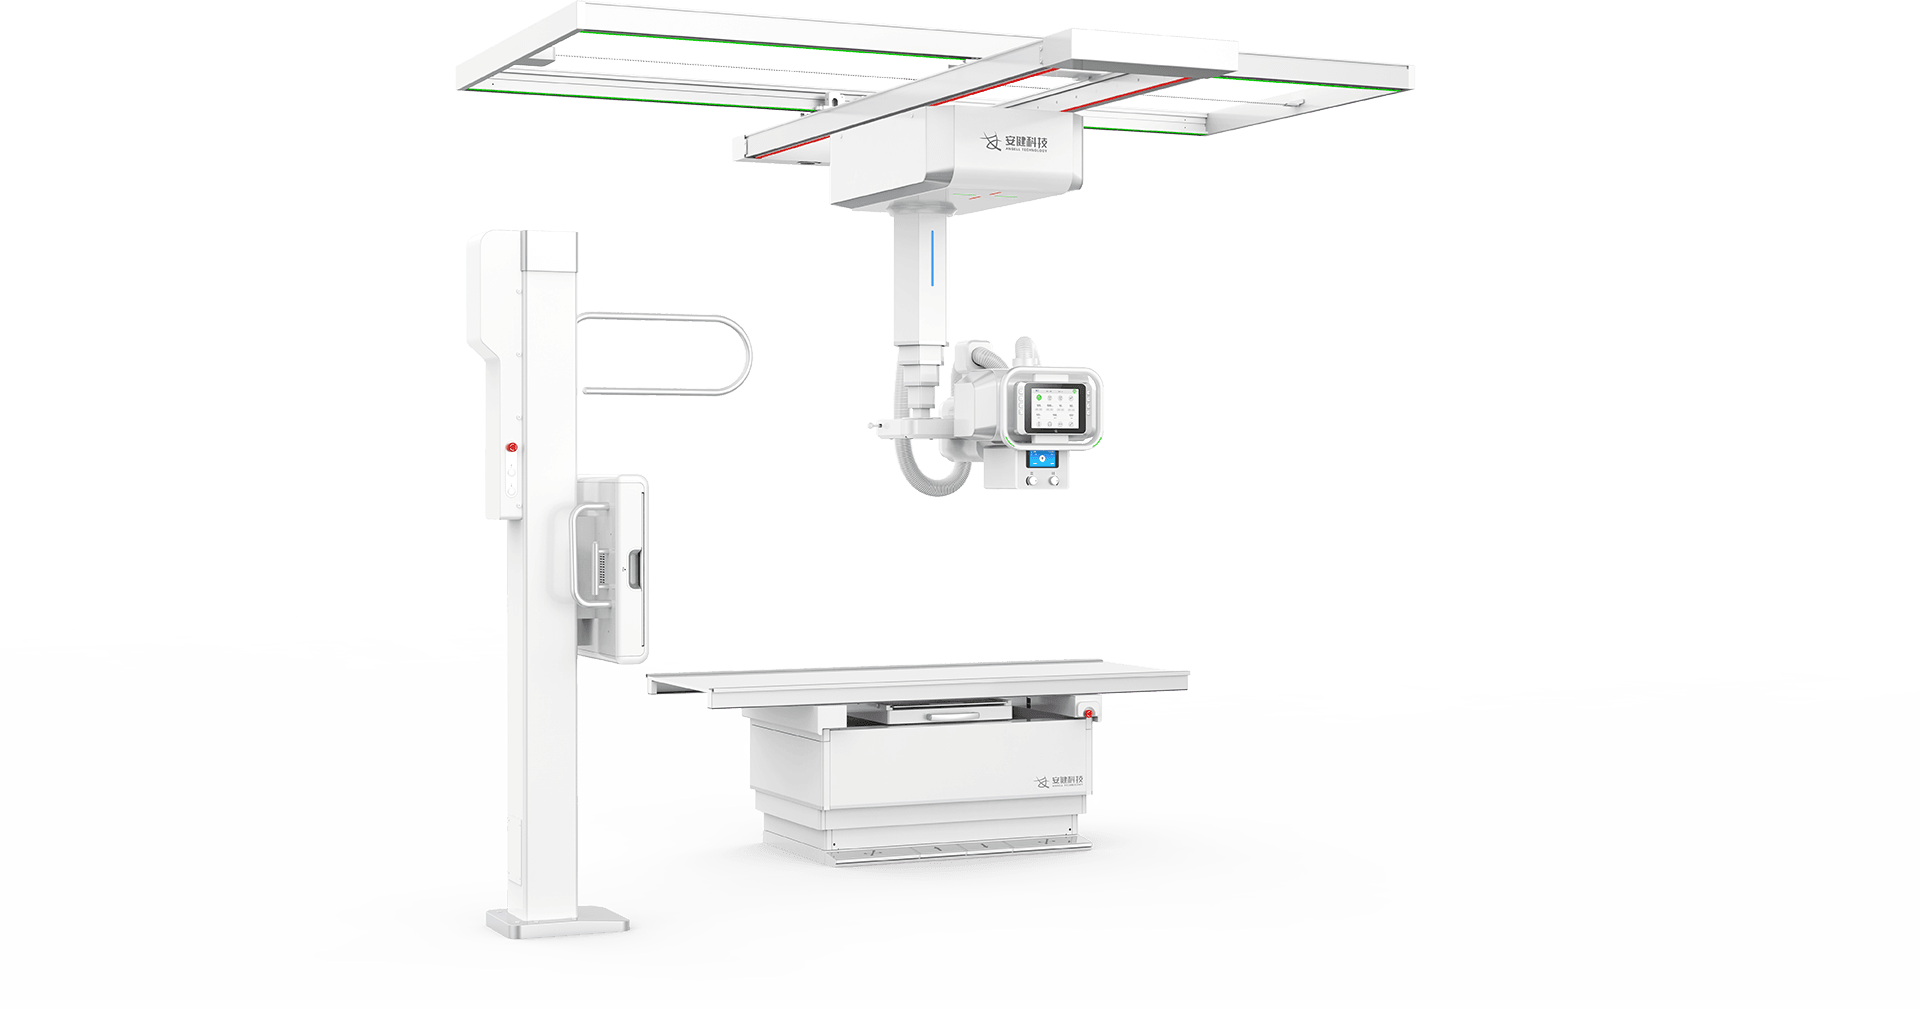

「 珠穆 」悬吊动态DR全球两大品牌之一

卓越动态成像技术

388vip太阳集团科技自主研发的动态探测器技术,让临床检查具备可视化条件,并实现快速高清点片,

精准捕捉病灶。实现从二维解剖成像到器官功能成像转变,让诊断更精准。

4D十轴联动运动系统

多功能悬吊式机械运动,全平衡稳定性设计,4D十轴联动技术,机架运动自如平稳,

配合电动升降床及多功能立式摄影架,轻松满足临床全体位摄影需求。

探测器、球管双向自动跟踪

探测器与球管可实现双向自动跟踪,

立卧位高精度实时同步,大幅提高临床检查效率。 -

立卧位一键切换、—键到位

全自动智能运动控制,射频信号双向接收设计,

实现立卧位一键切换、一键到位,简化操作,提升效率。 -

电动升降床

超大行程运动范围,灵活应对儿童、老人、外伤患者上下床。

配备嵌入式感应解锁系统,轻松调节床高并有效避免患者误触。

轻松高效操作流

多功能悬吊式机械运动,全平衡稳定性设计,4D十轴联动技术,机架运动自如平稳,

配合电动升降床及多功能立式摄影架,轻松满足临床全体位摄影需求。

动静双板自由切换

动态平板+静态平板双板配置,可实现毫秒级选板切换。

配合手自一体悬吊式机械运动系统,多体位拍摄转换轻松自如,大幅提升临床检查效率 -

卓越影像链

高压发生器

优质、稳定射线输出,满足大规模连续拍摄需求,长时间运行不宕机。 -

高热容量球管

优质、稳定射线输出,满足大规模连续拍摄需求,长时间运行不宕机。 -

平板探测器

千万级像素无线平板探测器,智能在线充电 -

影像工作站

高质量影像即时处理,动态影像可局部放大,回放时可任意段截取,保存并 PACS传输。